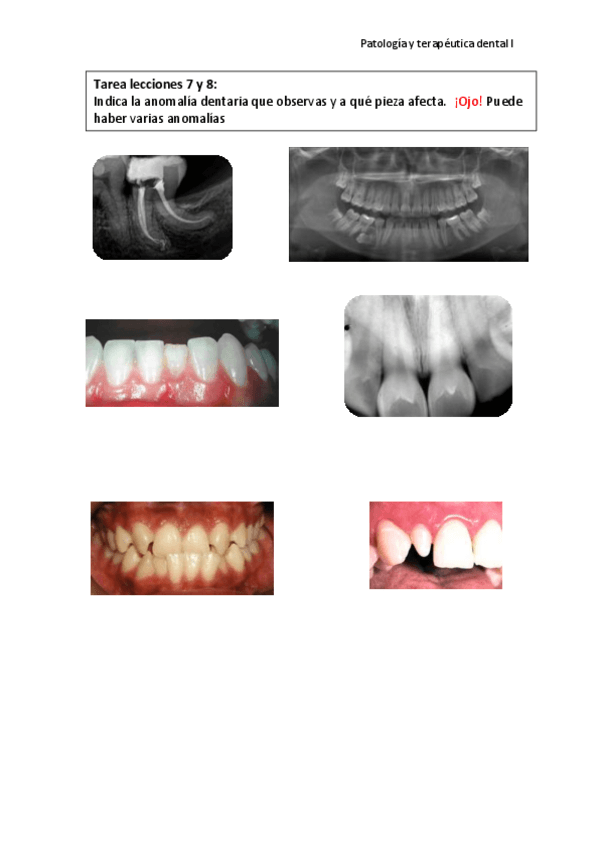

He publicado nuevos apuntes de 2º Patología y Terapéutica Dental I: PRÁCTICAS Y SEMINARIOS RESUELTOS

PRACTICA-ANOMALIAS-DENTARIAS.pdf